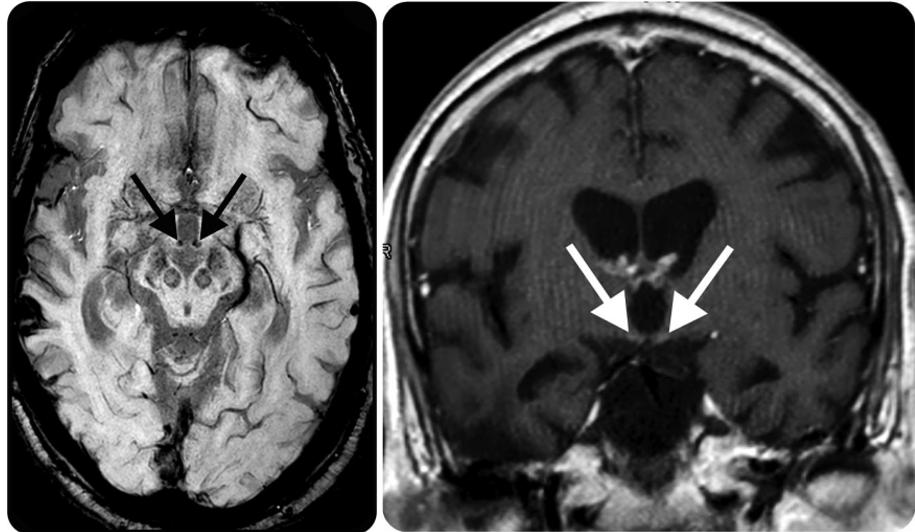

患者表現(xiàn)為意識障礙、肢體不自主運動、小腦性共濟失調、眼球震顫、雙側外直肌麻痹。顱腦MRI示:雙側小腦齒狀核(空箭頭)、前庭神經(jīng)核(白色箭頭)、展神經(jīng)核異常信號(短箭頭);中腦頂蓋、雙側黑質及乳頭體對稱性異常信號。